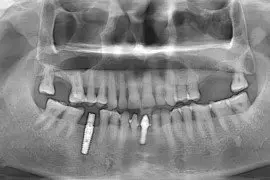

There are two types of sinus graft procedures:

[1] Indirect Sinus floor Elevation with placement of implant

[2] Direct Sinus Graft using modified caldwell luc technique

The maxillary sinuses are behind your cheeks and on the top of the upper teeth. Sinuses are like empty rooms that have nothing in them. Some of the roots of the natural upper teeth extend up in to the maxillary sinuses. When the upper teeth removed, there is often just a thin wall of bone separating the maxillary sinus and the mouth. Dental implants need bone to hold them in place. When the sinus wall is thin, it is impossible to place dental implants in this bone.

There is also a solution, its called sinus graft or sinus lift. The specialist or skilled implantologist enters the sinus from where upper teeth used to be. The thin paper like sinus membrane carefully lifted upward and donor bone is inserted into the floor of sinus. After several months of healing, the bone becomes the part of the patient’s jaw and dental implant can be inserted and stabilized in this new sinus bone.

Furthermore, If enough bone between the upper jaw ridge and the bottom of the sinus available to stabilize the implant well, sinus augmentations and implant placement can sometimes be performed as a single procedure. If enough bone is not available sinus augmentation will have to be performed first, then the graft will have to mature for several months, depending upon the type of graft material used. Once the graft material has matured, the implant can be placed.